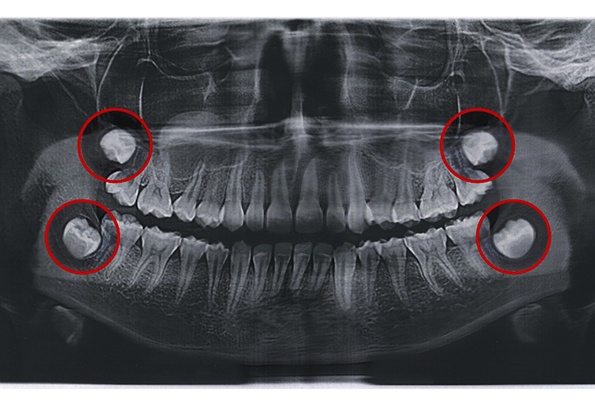

If you are between the ages of 16 and 25 and you start to experience pain towards the back of your mouth, you’ll want to get your mouth examined more closely by Dr. Jason Kaopua. In rare cases, wisdom teeth can erupt and be accommodated by the mouth. However, since the mouth is not typically large enough to do so, it can cause crowding. This negatively affects your smile and bite alignment. Furthermore, there are cases where wisdom teeth can become trapped underneath existing teeth. Without treatment, the tooth can easily become infected and harm other teeth.

Naturally, the procedure looks a bit different from patient to patient. While one patient may want sedation dentistry, the next may be happy with simply the numbing agent. While one patient may need one wisdom tooth removed, the next may have four impacted teeth. With all of that said, the procedure always starts by numbing the area of your mouth that we will be working on. Then, we will work to gently remove your wisdom teeth. If they are above the gumline, then we can carefully wiggle them free. If they are trapped beneath your gumline, then we will need to create a small incision and divide the teeth into several pieces first. Again, you won’t feel any pain, and we will continually check in with you to make sure you’re still comfortable.